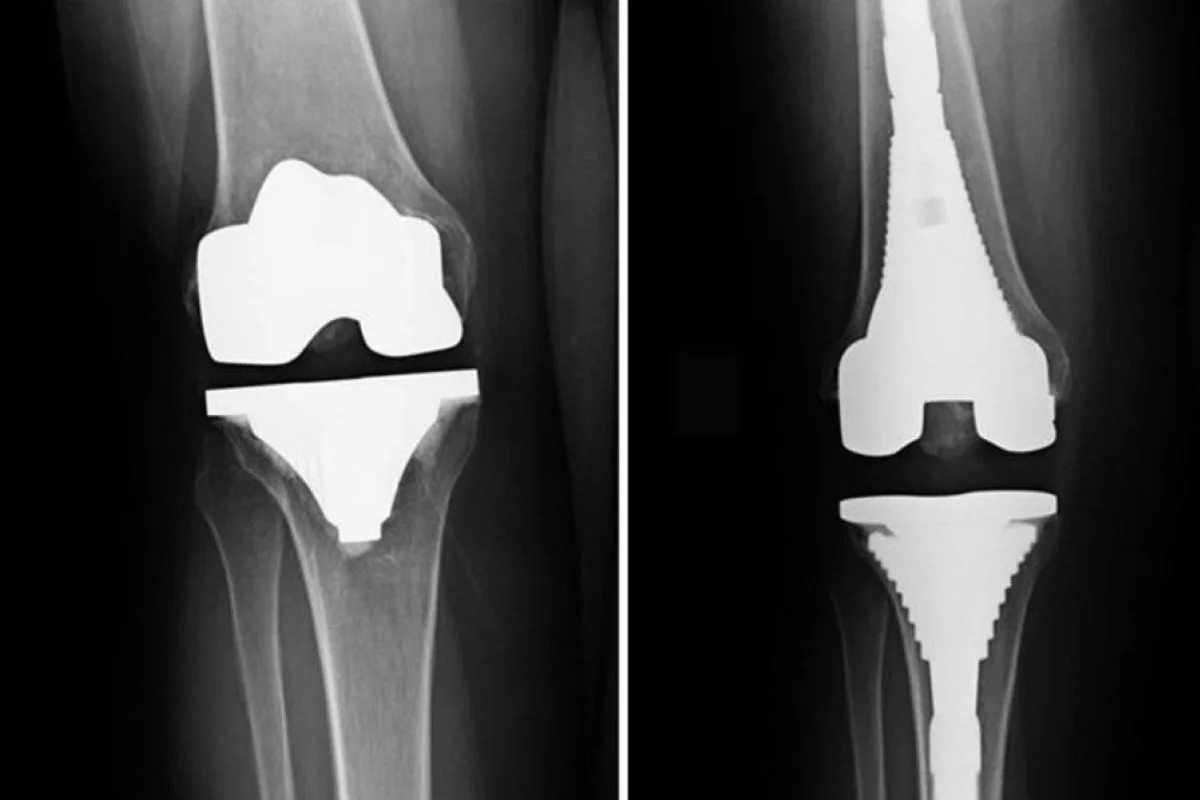

Total or partial knee replacement for arthritis or deformity.

Complex revision surgeries for failed implants or infection.